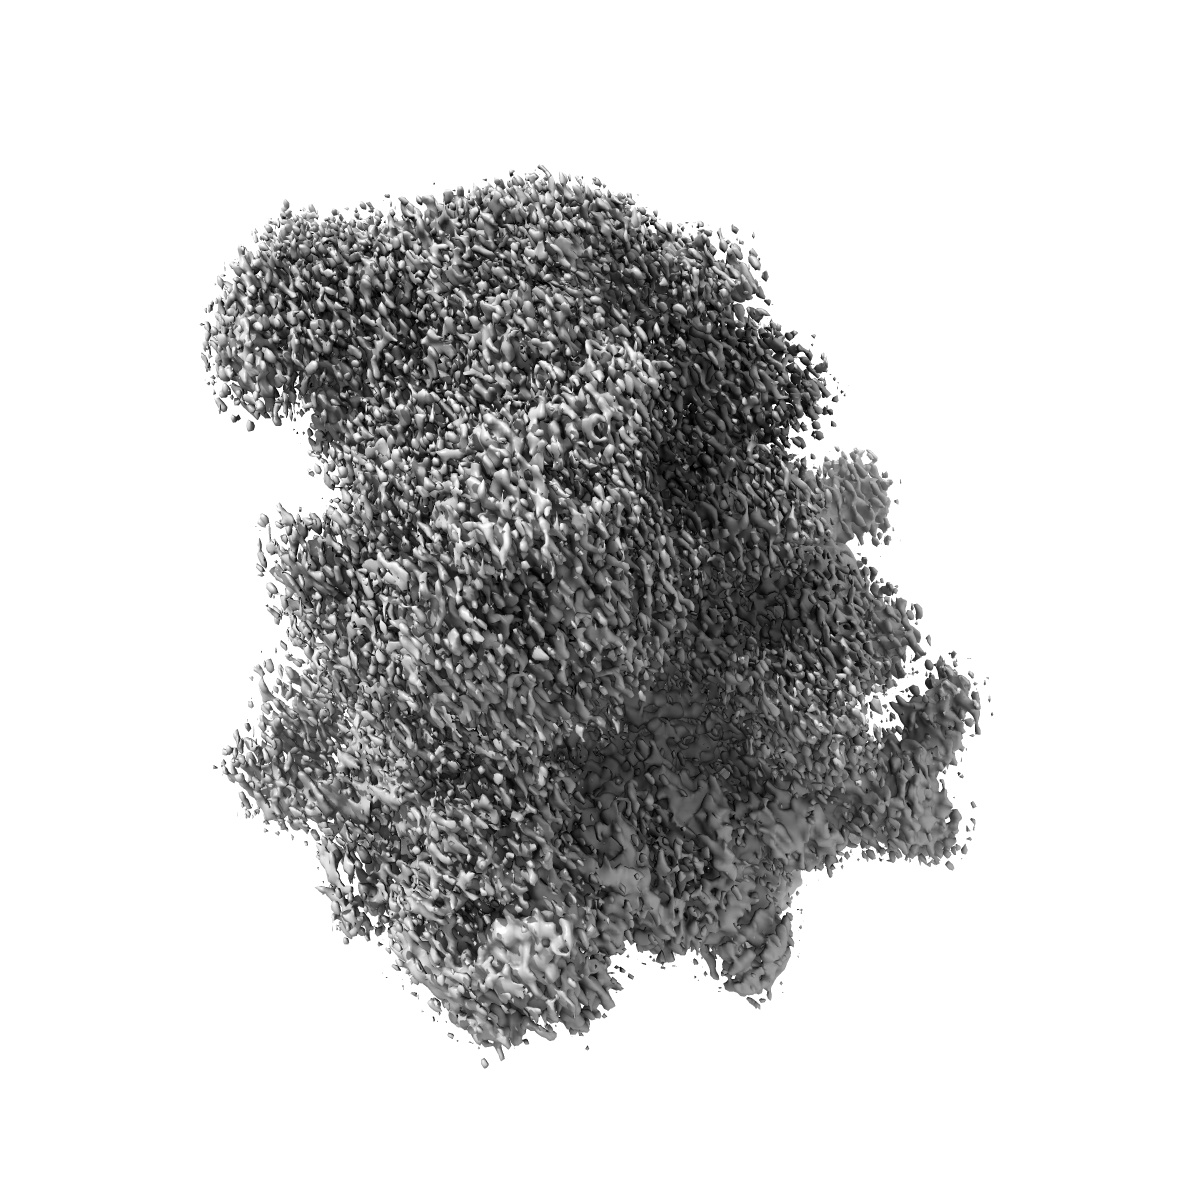

Erythromycin Resistant Staphylococcus aureus 70S ribosome (delta R88 A89 uL22).

EMD-10079

Single-particle

3.58 Å

Sample Organism: Staphylococcus aureus

Sample: Erythromycin Resistant Staphylococcus aureus 70S ribosome (delta R88 A89 uL22) in complex with erythromycin.

Fitted models: 6s13

Deposition Authors: Halfon Y, Matozv D

Exit tunnel modulation as resistance mechanism of S. aureus erythromycin resistant mutant.

Halfon Y, Matzov D, Eyal Z , Bashan A , Zimmerman E, Kjeldgaard J , Ingmer H , Yonath A

(2019) Sci Rep , 9 , 11460 - 11460

PUBMED: 31391518

DOI: doi:10.1038/s41598-019-48019-1

ISSN: 2045-2322